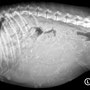

Sonntag Morgen, nachdem Glen tatsächlich ein paar Stunden Ruhe gefunden und tief geschlafen hat, geht's los. Um 9:00 platzt die Fruchtblase. Bei allen Würfen bisher dauerte es danach noch ganz genau 1 Stunde bis zur ersten Geburt. Diesmal nicht. Keine fünf Minuten! Und genau so flott ging's weiter. Im Abstand zwischen 30 und 90 Minuten drückte Glen ein Welpchen nach dem anderen heraus, ohne Hilfe, ohne Schmerzen, einfach so, souverän, wie im Bilderbuch. Öffnete die Fruchblase, leckte das Gesichtchen frei, biss die Nabelschnur durch, leckte ihre Babys sauber und trocken. Und eröffnete die Milchbar. Natürlich, in jeder Hinsicht.